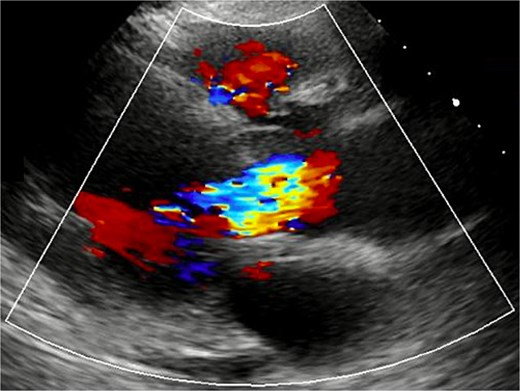

A 72-year-old woman with hypertension and dyslipidemia presented with progressive dyspnea. There was no family history of congenital heart disease. Electrocardiography showed sinus rhythm at 67 bpm and complete right bundle branch block. Contrast-enhanced computed tomography (CT) revealed a 25-mm saccular aneurysmal dilation arising from the right coronary sinus of Valsalva, without significant coronary artery stenosis (Fig. 1a and b). Transthoracic echocardiography (TTE) revealed severe AR (a regurgitant volume of 91 ml, an effective regurgitant orifice area of 0.54 cm2, and a maximum regurgitant velocity of 3.4 m/s). Left ventricular systolic function was preserved, with a left ventricular end-diastolic/systolic diameter of 55/38 mm, and no ventricular septal defect was detected (Fig. 2). Although unruptured, the aneurysm was giant and associated with severe, symptomatic AR; therefore, surgical intervention was indicated. Given an acceptable operative risk (preoperative European System for Cardiac Operative Risk Evaluation II, 3.48%), a modified Bentall procedure was performed.